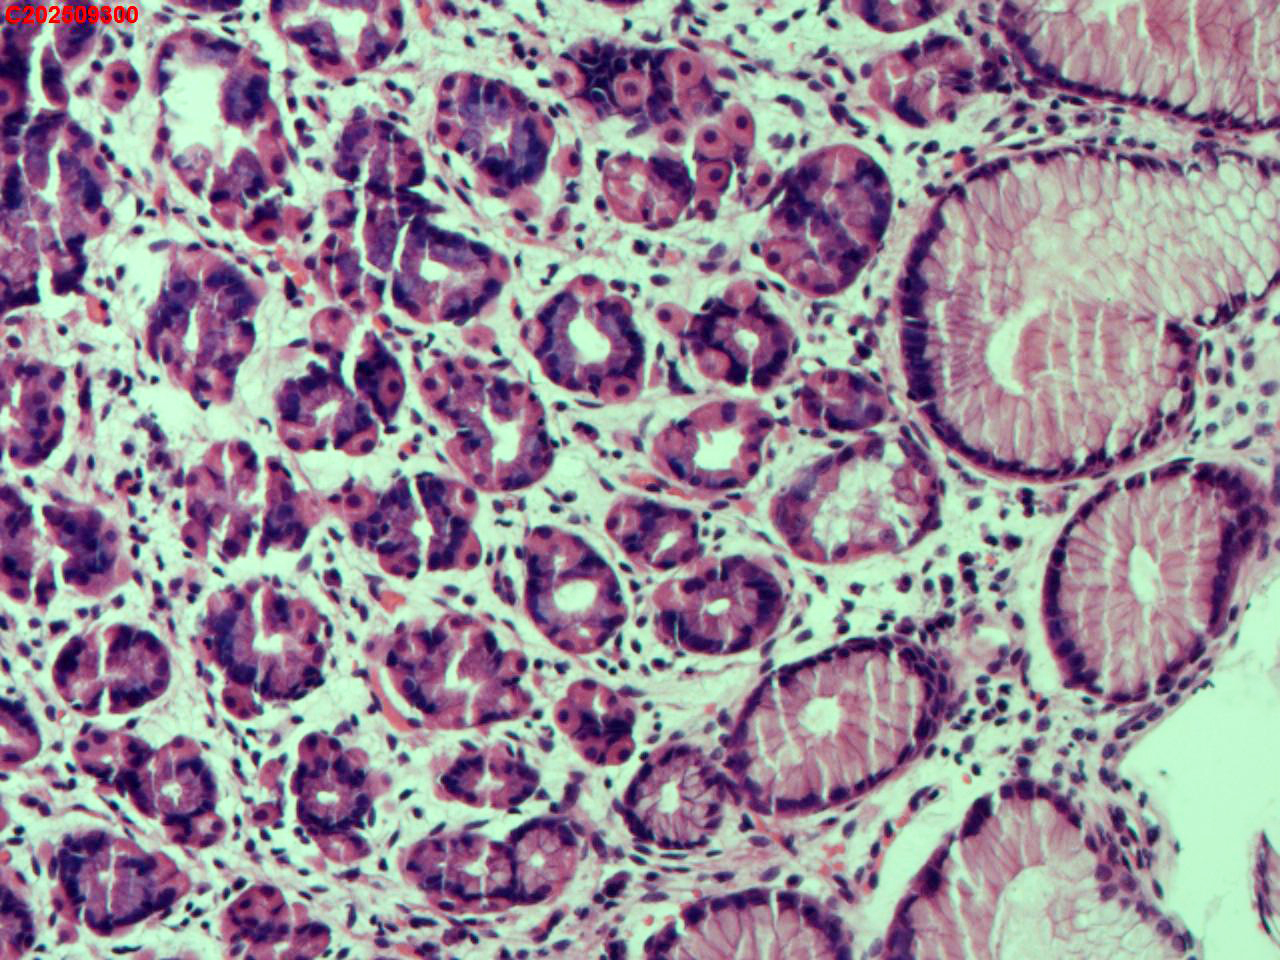

胃底粘膜

性别

女

年龄

44岁

临床诊断

胃息肉

一般病史

体检

标本名称

大体所见

胃底:可见一枚直径约2mm的半球形息肉。

增生性息肉